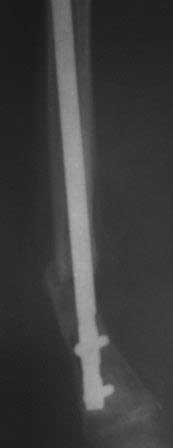

Уважаемые коллеги.Очень прощу помочь в одном сложном деле. Девочка 2005г.р. В середине 2008 г падает с велосипеда с дедом, возможно был перелом н/з костей левой голени, лечение у знахаря-табиба, но ребенок не смог бегать, часто падал, начал хромать. Май 2009г. обратились к нам, установлен д-з « вялоконсолидирующаяся перелом н/з б/берцовой кости, несросшийся перелом м/берцовой кости со смещением по ширине». Мы решили гипсовая повязка и ходьба с нагрузкой, но по категорическому требованию родителей исправить деформацию м/берцовой кости, произвели операцию ( на свою голову )»о/ репозиция и и/м фиксация спицами м/берцовой кости». Теперь началась самая интересная история! Ч-з недели две в обл. п/о раны м/берцовой открылась свищ с кровянистым выделением, гноя не было, на р-грамме лизис концов отломков м/берцовой кости, к-рый начал прогрессировать, консультирована онкологами, цитология, с подозрением направлена в центральные институты, сделана КТ, онкологическое исключили, в августе попали в остеомиелитический центр, где произведена резекция м/б на протяжение 6-7см, все зажило и выписали (снимок-1). 2010г в мае повторно получила травму, наложена гипсовая повязка (снимок-2) и через 1-2 месяца в одном из центральном институте произведена КДО аппаратом Илизарова , который снят ч-з три месяца (снимок-3) и долго ходила на костылях-мать заставила, как начала наступать, появилась деформация, заказали ортез и так ходила, но деформация прогрессировала, Обратилась к нам в апреле 2012г,(снимок-4) произведена постепенная коррекция на аппарате, и замена на БИОС 01.03.12г плечевым гвоздем, ЭОП нет, поэтому осталась несколько антекурвация (снимок-5), ребенок ч-з неделю начала ходить.Повторный осмотр 22.06.12г- деформация усиливается, за три месяца сращение очень слабое.(снимок-6). (Жаль что многие р-снимки не сохранились, мать обещала хотя бы часть найти)!Что теперь делать? Удалить дистальные винты и пробовать исправить на аппарате, или гвоздь убрать , коррекция на аппарате и после рассверливания повторный БИОС? Уважаемые коллеги, какие варианты предлагаете? С уважением Абдурашид.